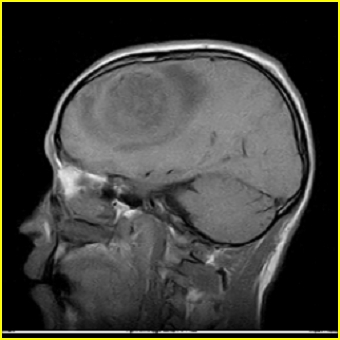

男,45岁,头部剧烈疼痛伴呕吐5天。

右侧额叶见较大的类圆形长t1信号环绕等t1环影,长t2信号环绕短等t2环,周围见明显水肿占位征,中线结构左移,男,45岁,头部剧烈疼痛伴呕吐5天。

右侧额叶,见一占位病灶,t1像病灶、水肿长t1;其间为短t1环行信号。t2像病灶、水肿长t2,其间为短t2环行信号。占位效应明显,中线左移,右测脑室受压闭塞。结合患者发病较急。首先考虑:右侧额叶脑脓肿形成。鉴别:1、转移瘤,多发多见2、胶质瘤。建议增强

t1加权肿瘤呈低信号,肿瘤壁呈等信号.t2 加权时肿瘤呈高信号,肿瘤壁呈等信号.

考虑1脑脓肿.2恶性胶质瘤.